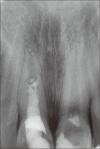

Traumatic injuries to an immature permanent tooth may result in cessation of dentin deposition and root maturation. Endodontic treatment is often complicated in premature tooth with an uncertain prognosis. This article describes successful treatment of two traumatized maxillary central incisors with complicated crown fracture three months after trauma. The radiographic examination showed immature roots in maxillary central incisors of a 9-year-old boy with a radiolucent lesion adjacent to the right central incisor. Apexogenesis was performed for the left central incisor and revascularization treatment was considered for the right one. In 18-month clinical and radiographic follow-up both teeth were asymptomatic, roots continued to develop, and periapical radiolucency of the right central incisor healed. Considering the root development of these contralateral teeth it can be concluded that revascularization is an appropriate treatment method in immature necrotic teeth.